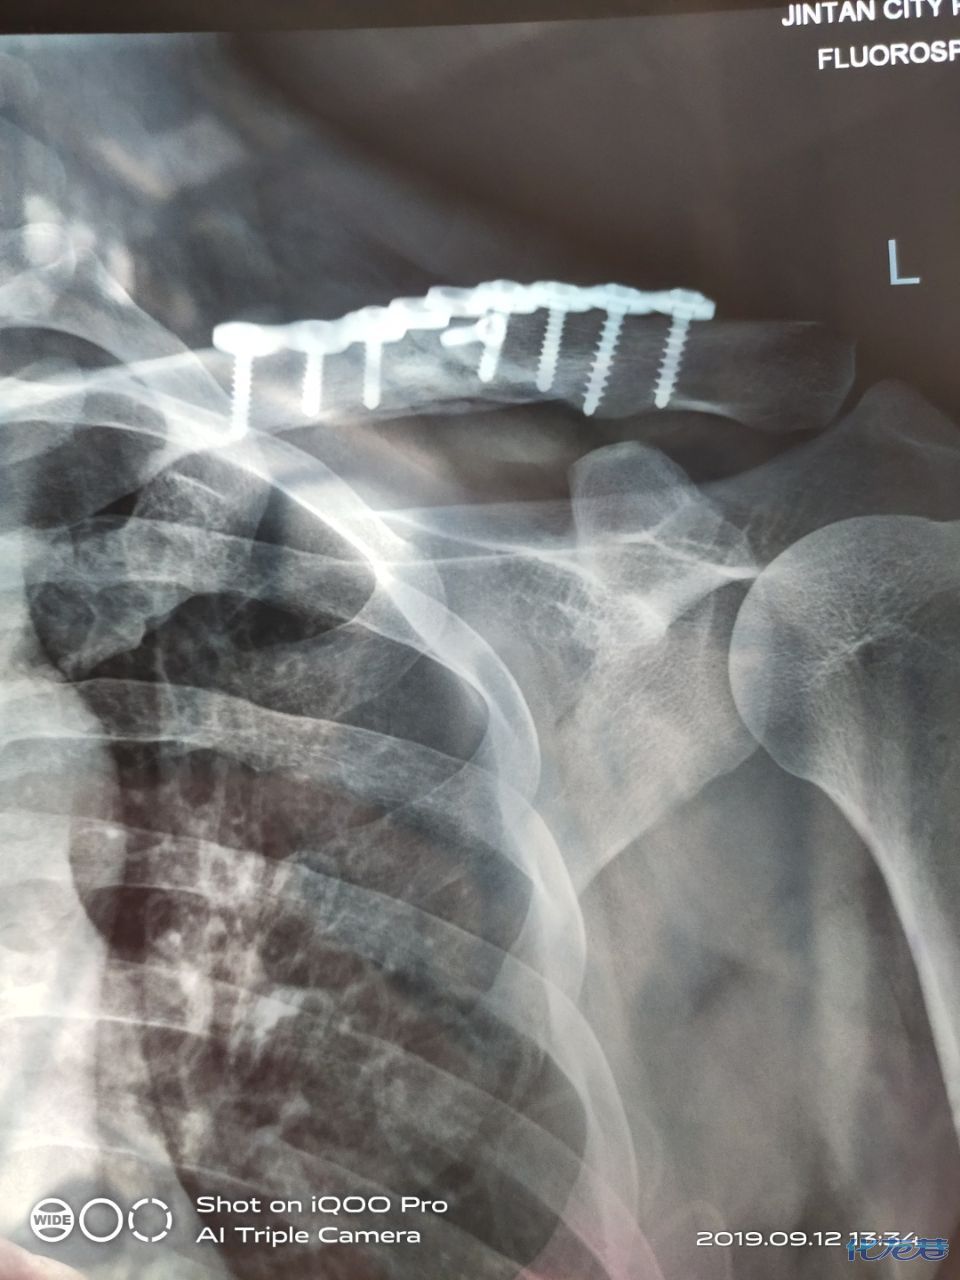

锁骨骨折两个月的图片

锁骨骨折两个月的图片,锁骨骨折睡姿

锁骨骨折x光图片

锁骨骨折手术